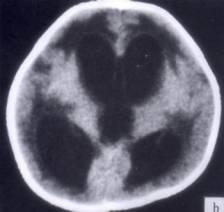

病历摘要:??患者女性,10岁。结核性脑膜炎愈后8月,头痛伴恶心呕吐1周,并渐加重。体检:神清,精神差,反应迟钝,双眼底视神经乳头水肿,双眼外展差,余未见...

问题 病历摘要:??患者女性,10岁。结核性脑膜炎愈后8月,头痛伴恶心呕吐1周,并渐加重。体检:神清,精神差,反应迟钝,双眼底视神经乳头水肿,双眼外展差,余未见明显异常。 下列关于颅内压增高的叙述哪些是正确的?